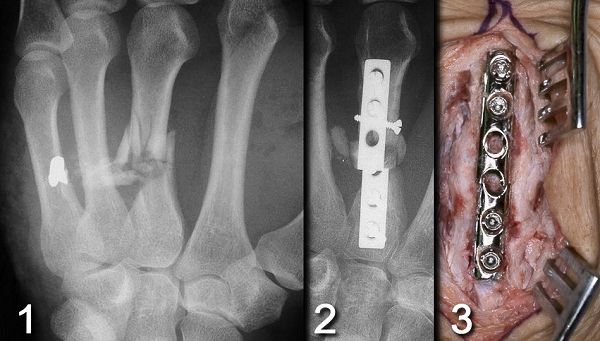

Figure Legend: High velocity gunshot wounds

result in a wide zone of soft tissue injury. Fracture is associated with

high-energy injuries (1) are more likely to have complications of delayed

union, nonunion and hardware failure (2,3).